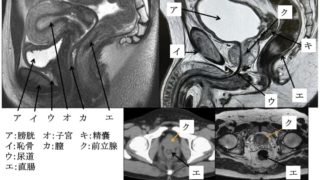

59 生殖器の腫瘍で最も脂肪を含む頻度が高いのはどれか。

1.陰茎腫瘍

2.子宮頸癌

3.精巣腫瘍

4.前立腺癌

5.卵巣腫瘍

正答

無理だと思う

こういうのいちいち覚えだすとキリがないので解けなくていい

放射線科医は知らなきゃいけませんが、技師の国家試験レベルではない

泌尿器・生殖器系 正常解剖 / 臨床病理

泌尿器・生殖器系 正常解剖腎臓・腎臓の構成(77pm53、76pm61、73pm16、72pm50、66.2) 皮質+髄質(腎錐体)+小腎杯+大腎杯+腎盤(腎盂)+(尿管へ) ・皮質:腎小体(ボーマン嚢+糸球体)+近位尿細管・髄質:ヘレンループ+遠位尿細管+集合管・ネフロン:腎小体と尿細管で構成 腎臓の構造上・機能上の単位・機能(64.10):「血圧・体液量・塩酸基平衡の調整」 「老廃物排出」 ・位置:右が下、左が上・重さ:130g×2・尿の生成(67am55、68pm55、62.16、60.10) 腎動脈 :腎静脈の後方に位置する   ↓ 腎血流量:1200ml/min  ↓  腎小体(糸球体からボーマン嚢へ) :血液をろ過し原尿にする  ↓(血液から血球や高分子蛋白を除いたもの)  ↓ 原尿:100~150ml/min  ↓    150L/day  ↓                 近位尿細管(毛細血管へ) :ブドウ糖(100%)と水分・無機塩類の大部分の再吸収  ↓ (能動輸送)  ↓             ヘンレループ(毛細血管へ) :水分(10~20%)の再吸収  ↓ ...